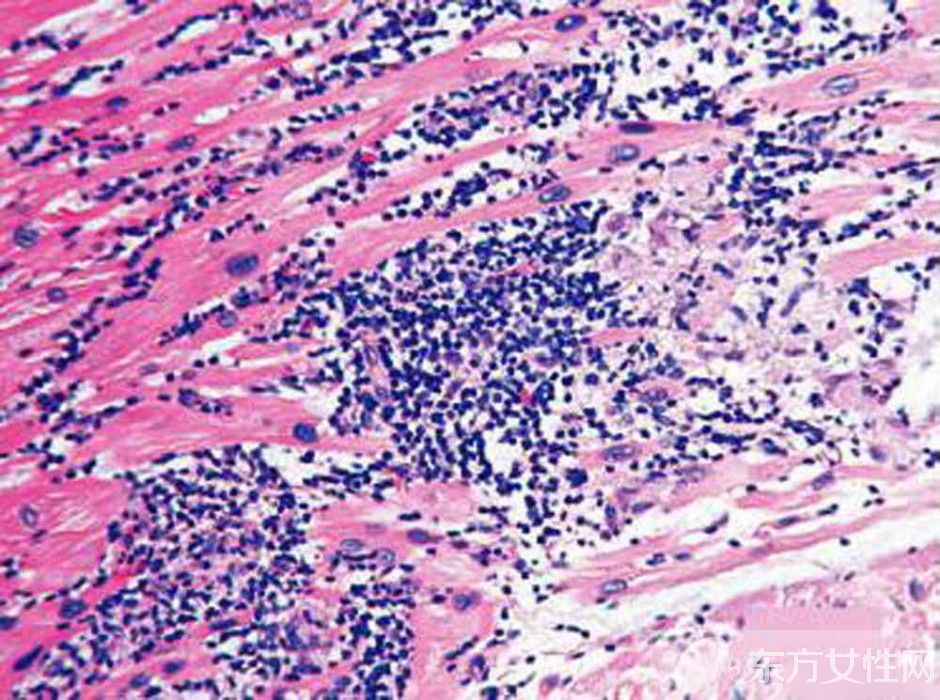

心肌炎是怎么引起的?

3、细菌感染

研究发现,当人体受到细菌和病毒混合感染时,可能起协同致病作用。还有在妊娠期间,妊娠可以增强病毒在心肌内的繁殖,所谓围产期心肌病可能是病毒感染所致。